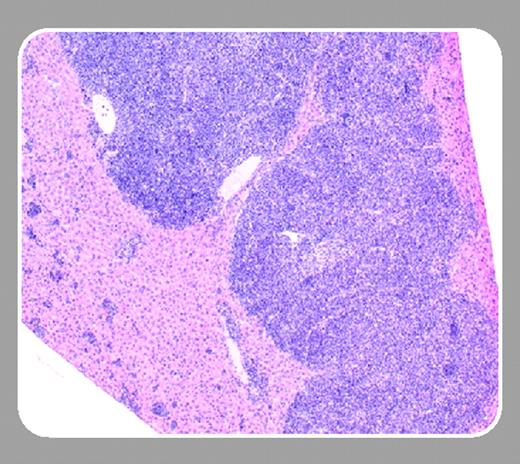

FL is also the most common B-cell lymphoma naturally arising in old mice and in Eμ-Pim-1 transgenic mice. White pulp expansions of sIgM+/B220+/CD19+ GC B cells usually begin in the spleen and may contain large (centroblasts, immunoblasts), small (centrocytes), or a mixture of large and small tumor cells that lose the usual GC spatial relationships. Unlike human FL, naturally occurring mouse FLs are not associated with Bcl2 gene overexpression and do not display a typical follicular pattern. Despite several attempts, a BCL2-based model of FL has not been generated in mice, until now.

In this issue of Blood, Egle and colleagues (page 2276) describe a new model of FL by Bcl2 overexpression using VavP control sequences. About 15% to 25% of mice developed a syndrome resembling autoimmune glomerulonephritis that was strain dependent. However, 37% to 50% of mice developed FL by 18 months of age following a florid GC hyperplasia.2 Other hematologic tumors occurred at lower frequencies, including plasma cell tumors, lymphoblastic or large B-cell lymphoma, thymic lymphoma, and histiocytic sarcoma. Interestingly, levels of the Bcl2 transgene expression were independent of lymphomagenesis; rather, CD4+ T-cell help appeared essential for FL.